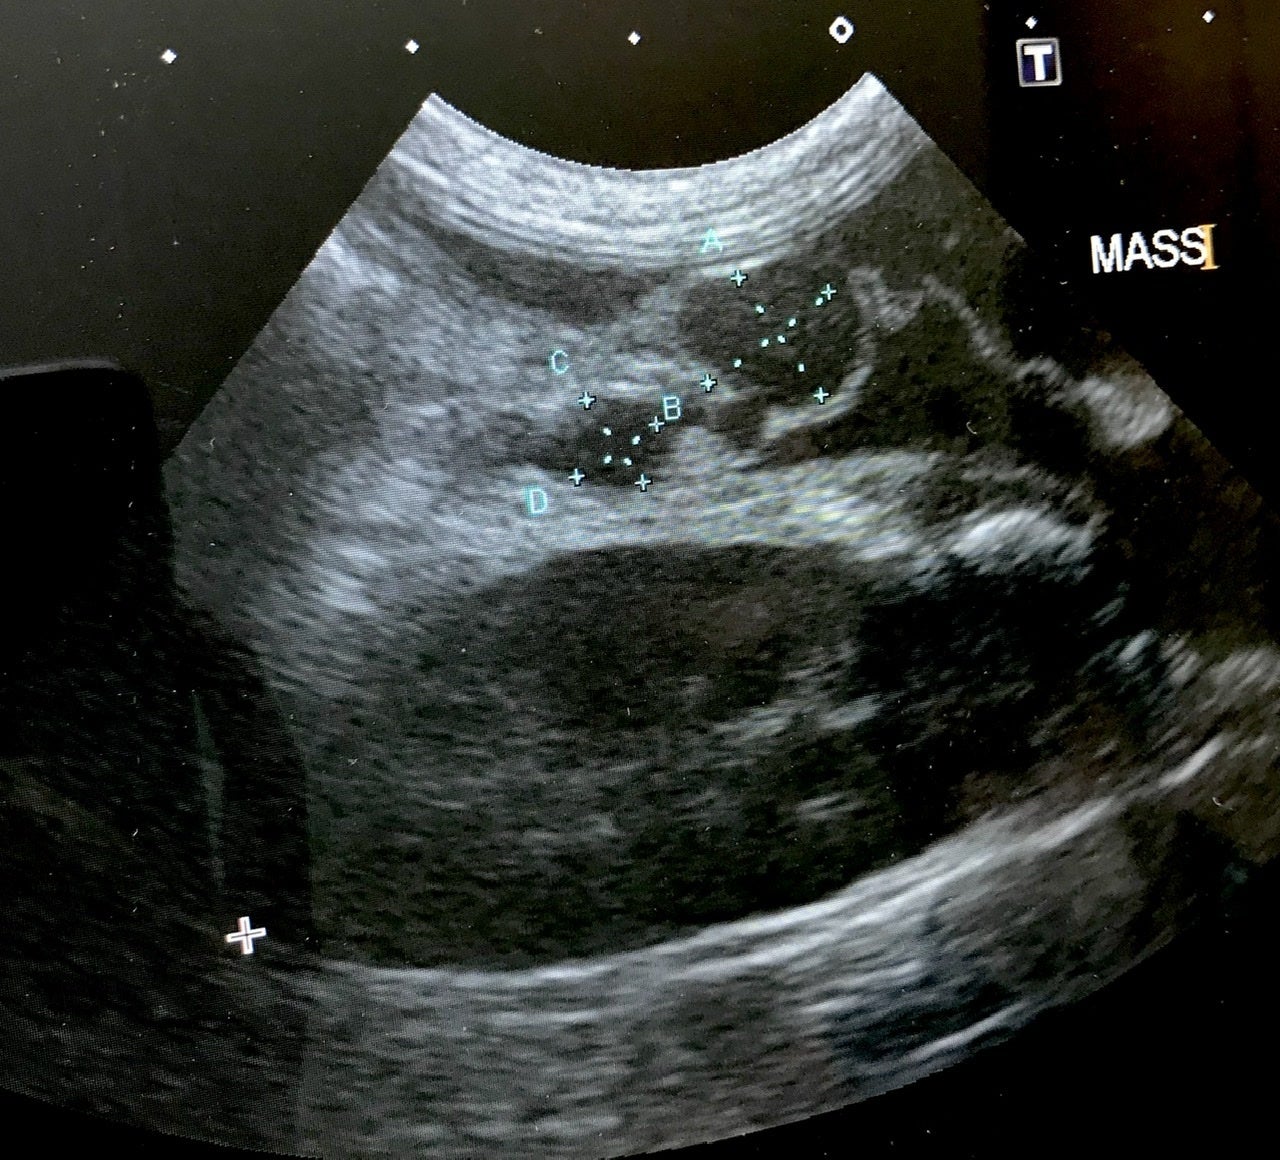

お腹に肉芽腫のようなものがあるとエコー写真を見せられ3センチほどの塊が写っていました。

検査で血液検査、エコーを見ながら説明してくださり「FIP確定です」と宣言されました。腹水が溜まっているのと肉芽腫があることからウェットドライ混合タイプでした。

↑肉芽腫

↑腹水